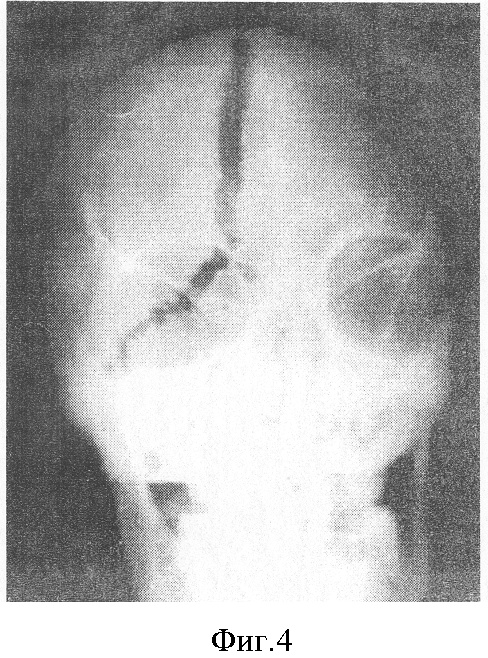

В случаях, когда промерзание головы начиналось с затылка и теменных областей, повреждений костей черепа мы не наблюдали. Если же промерзание трупа начиналось с области шеи, а затем промерзала голова, то во всех этих случаях мы наблюдали повреждения костей черепа (см. фиг.4).